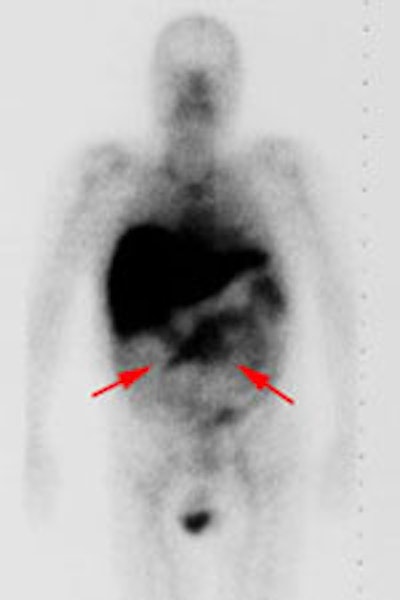

Recurrent colorectal carcinoma: The patient shown below had a history of colon cancer and was being evaluated for a rising CEA-level. CT scan had been interpreted as negative. The OncoScint exam demonstrated focal abnormal tracer activity within the mid-abdomen (red arrows). This activity persistent on delayed images following administration of a bowel prep. At surgery the patient was found to have omental disease and involved lymph nodes corresponding to the abnormality on the OncoScint exam. Even in retrospect, the CT images did not demonstrate definitive abnormality (Click CT for more images) |